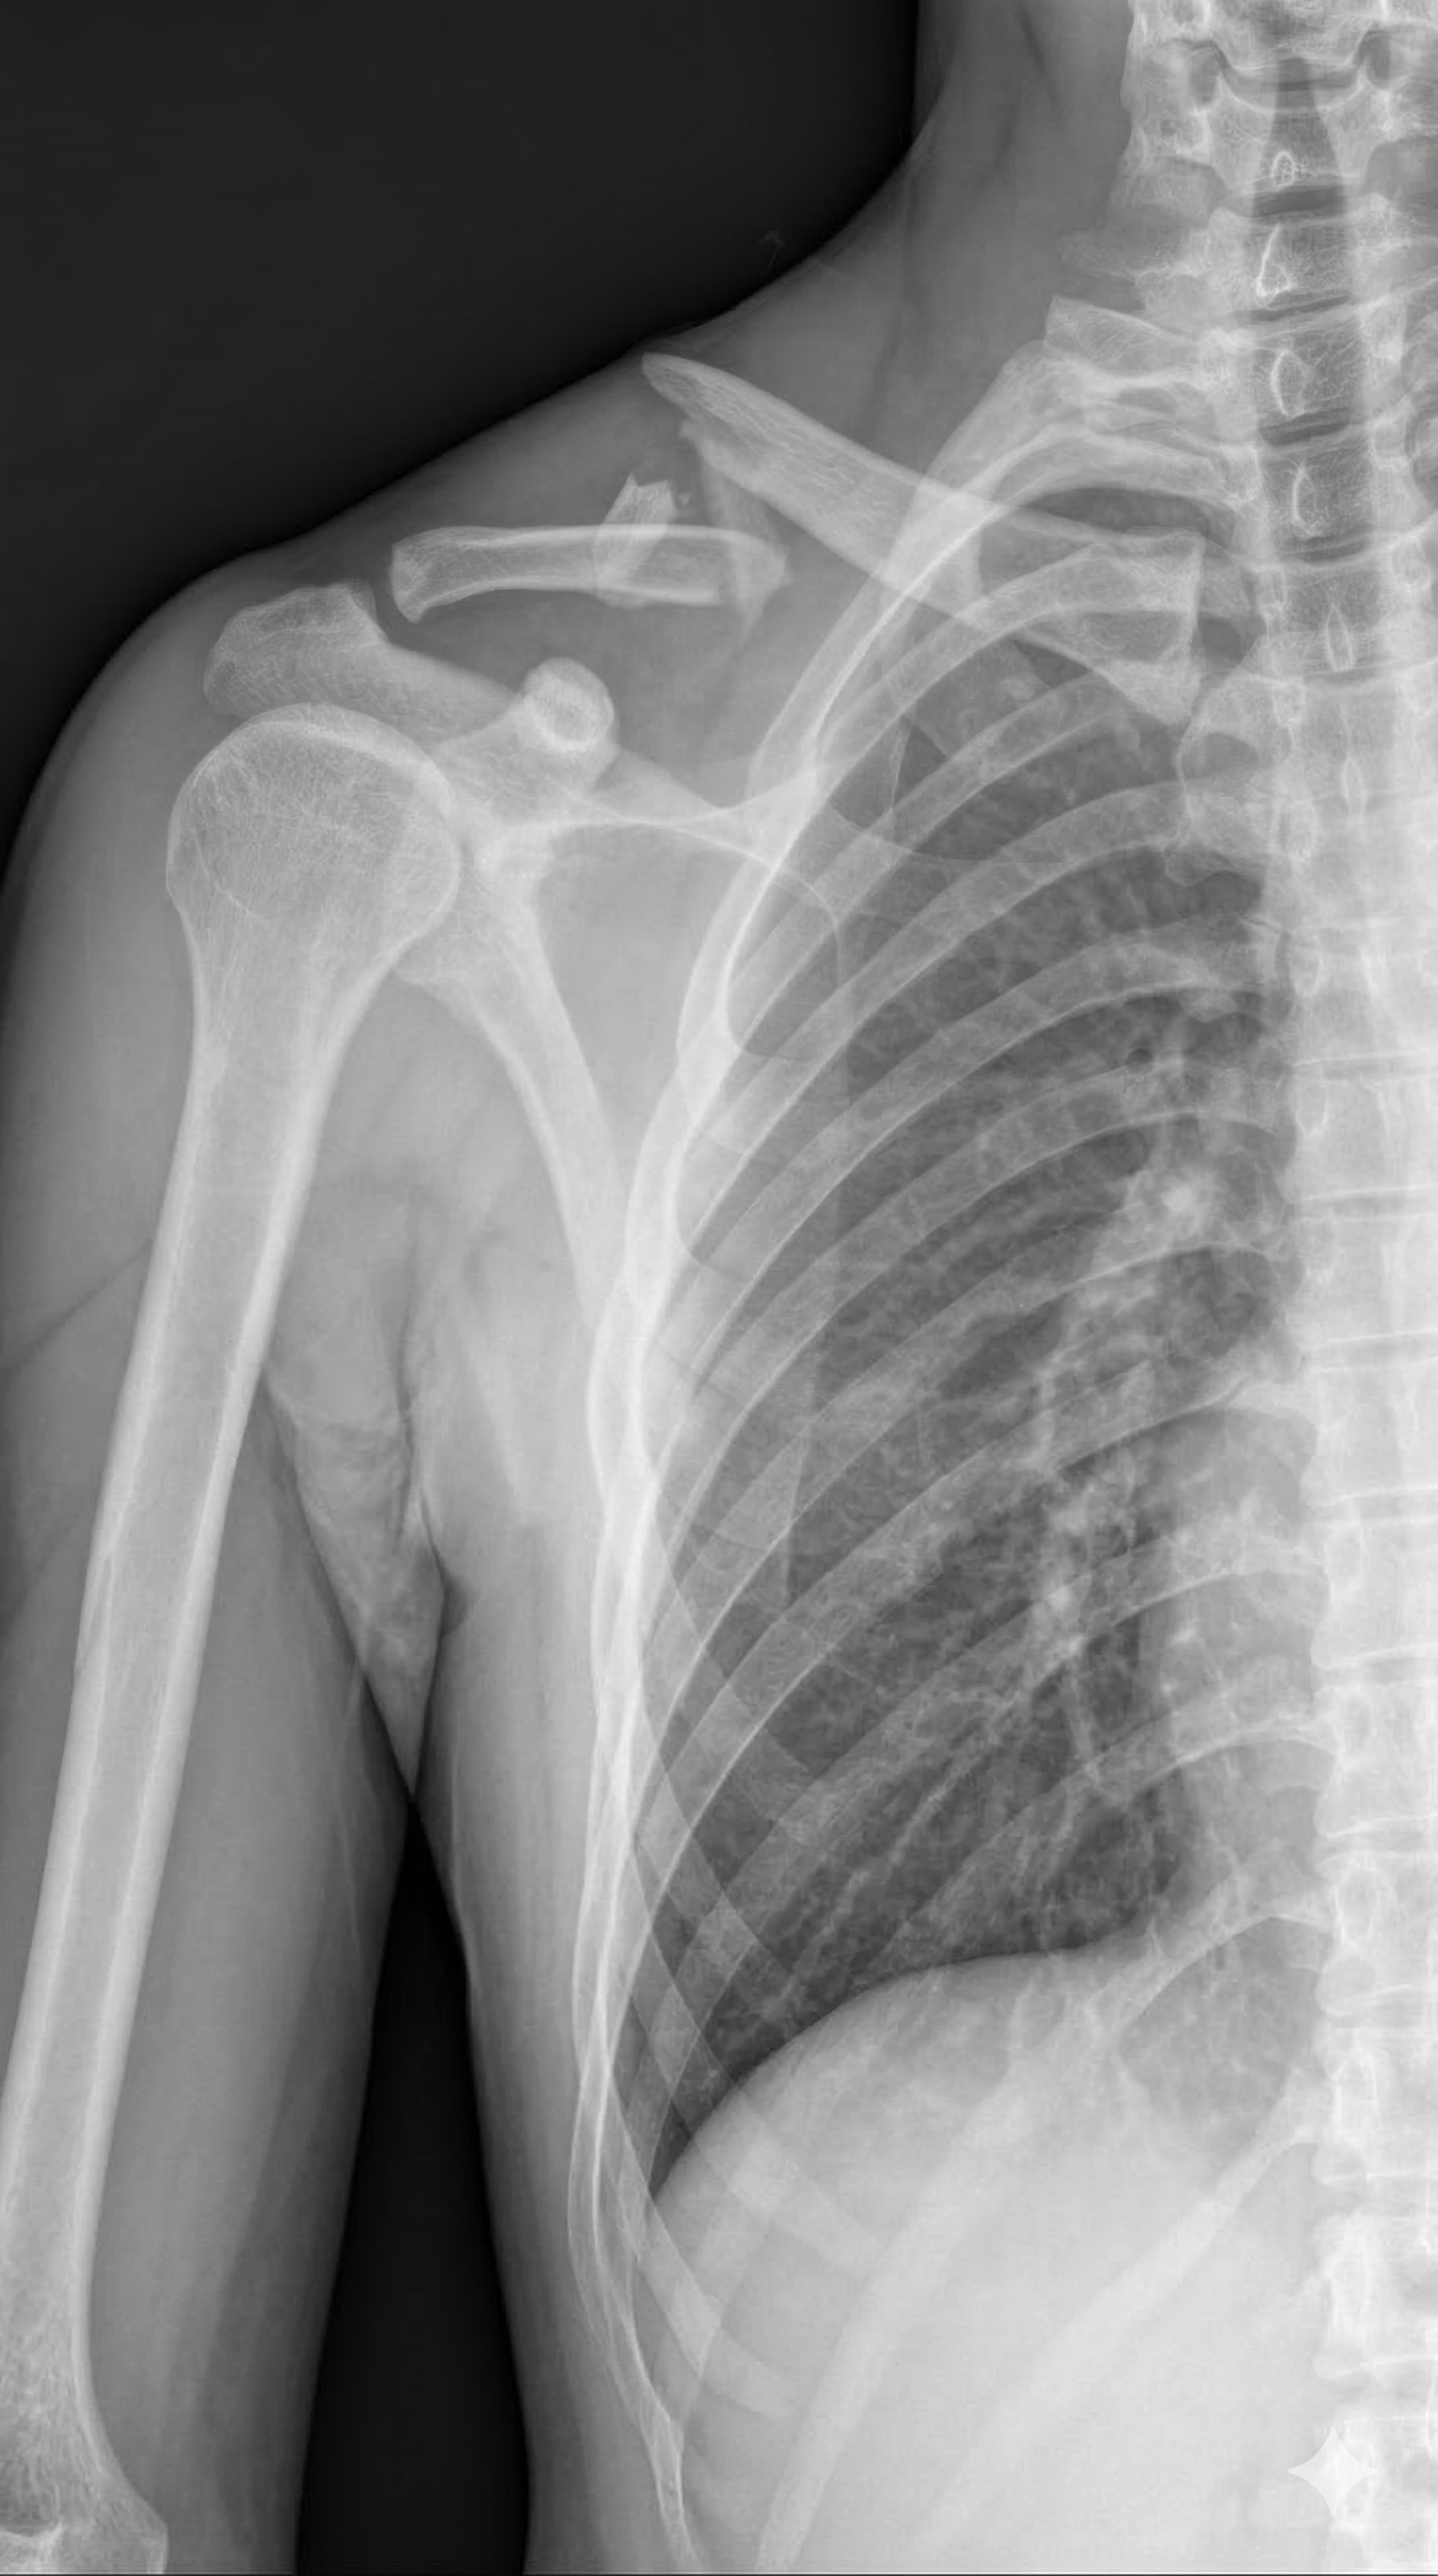

I've already paid 150,000 Baht in hospital bills. My foot was operated on, but the first hospital ignored my broken shoulder — telling me it would "fix itself." It won't. I got a second opinion and now need urgent shoulder surgery.

As a programmer, my hands and arms are everything. Without this surgery, I cannot work. My hand has been permanently numb since the accident. The doctors cannot yet confirm if this will be reversible.

It is uncertain if I will be able to walk again or my hands have permanent damage.